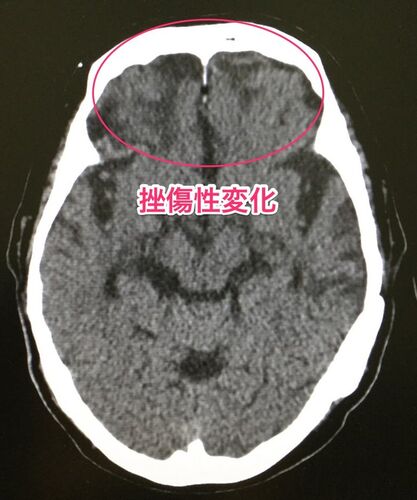

近医からの紹介で来られた方。主なお悩みは、「頻尿」。 加齢や頭部外傷の影響でわずかにアセチルコリンが欠乏していたところに、過剰な量のアリセプトが入ったことで頻尿が惹起されていたと考えている。*1 *1:アセチルコリンが減ればアルツハイマーと短絡してはい…